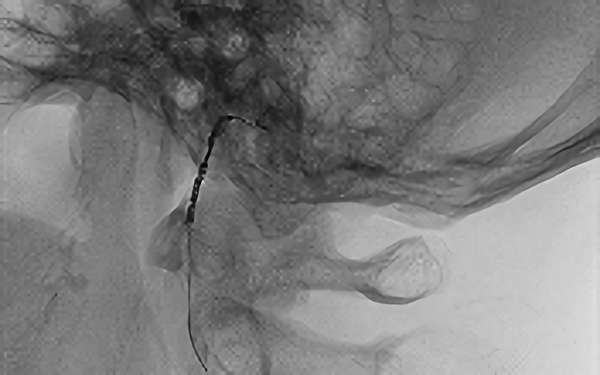

'25年4月

くも膜下出血

右内頚動脈脳動脈瘤破裂

50代

救急外来

No.1544 手術前

No.1544 手術中

No.1544 手術後